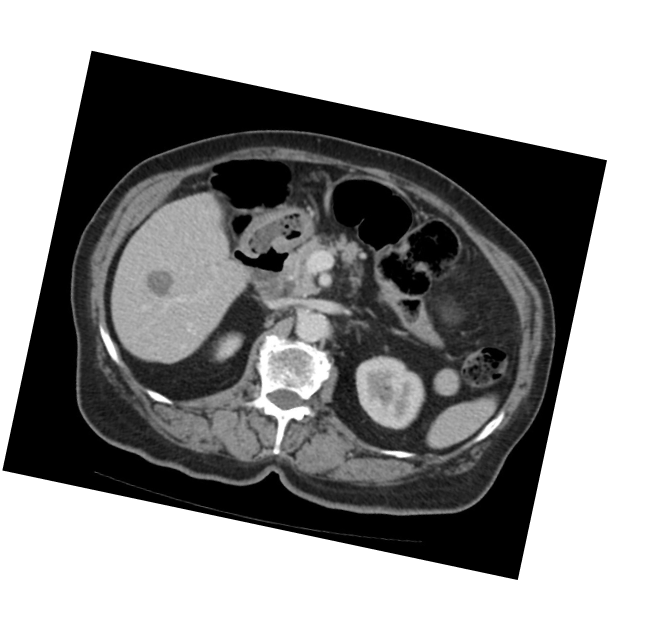

КТ брюшной полости и малого таза:

В печени выявляются гиподенсные очаги: субкапсулярно

в С7/6 печени 50×25мм, в С6 — 44×38мм, в С5 — 11×9мм,

с С7 — 11×7мм, в С3 — 15×14мм